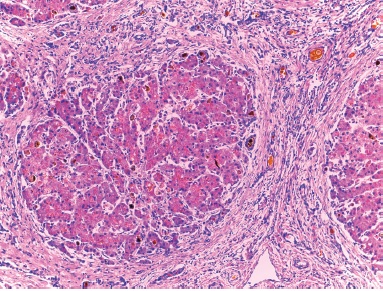

El examen del hígado mostró un cuadro mixto de cirrosis obstructiva con colestasis acentuada y una fibrosis de bandas gruesas y limpias, con hiperplasia hamartomatosa de conductos (Figura 3) con un patrón que recordaba a la fibrosis hepática congénita; condición, sin embargo, en la que no suele haber colestasis ni insuficiencia hepática. El fragmento de hígado resecado no incluyó el hilio pero en uno de los cortes se apreció un conducto biliar mayor dilatado y sin epitelio pero con contenido biliar (Figura 4). Este se encontró en un espacio porta mayor y nos sugirió la posibilidad de una enfermedad de Caroli, que sería una malformación de la placa ductal con colestasis.1-3 Como existió evidencia de que no hubo obstrucción biliar extrahepática –la vesícula presente y las heces estuvieron pigmentadas– este caso pareció corresponder a una malformación de la placa ductal con componentes de enfermedad de Caroli y de fibrosis hepática congénita; para esta combinación de dos expresiones de malformación de la placa ductal se ha propuesto el nombre de síndrome de Caroli.4 Los espacios porta periféricos mostraron colestasis acentuada con cambios inflamatorios incipientes en colangíolos (Figura 5) y en el parénquima hepatocelular marcada colestasis y transformación de células gigantes como respuesta a la obstrucción (Figura 6). El nódulo prominente descrito sobre la superficie del hígado en el corte tuvo más o menos el mismo aspecto que el resto y probablemente fue un foco de regeneración nodular. La presencia de regeneración y los datos de obstrucción biliar nos permiten proponer un componente de cirrosis obstructiva superpuesto a la patología de base que serían la fibrosis hepática congénita y los cambios de Caroli.